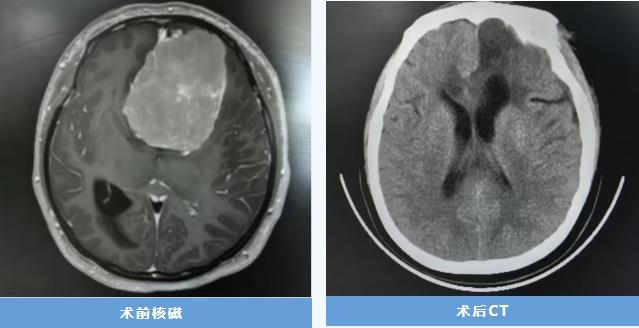

三十余岁的孕妇潘女士(化名)在怀孕38周时,突发头痛并出现意识间断模糊,伴有持续性头晕、视力模糊,甚至无法站立。急诊CT检查提示,其左侧额颞部存在一个约 7cm×6cm×7cm的巨大占位性病变,占据了颅内约四分之一的空间。妊娠分娩过程中的血压波动,极易诱发脑疝,直接危及生命。

术后患者恢复良好,神志清楚、言语流利、四肢活动自如,复查CT显示肿瘤完全切除,病理证实为脑膜瘤。目前患者已痊愈出院,母子平安。